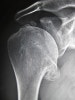

영상 검사

AP, axillary X-ray 검사가 필요합니다.

연골파괴로 인한 관절간격 좁아짐은 axillary view에서 가장 잘 나타납니다.

초기 사진에서는 변화가 뚜렷하지 않습니다.

골관절염을 시사하는 다른 X-ray 이상소견은 상완골두가 편평해짐, 아래쪽 골극 형성, 관절오목의 뒤쪽 침식입니다.

X-ray : 어깨 관절염(Shoulder arthritis, glenohumeral arthritis)